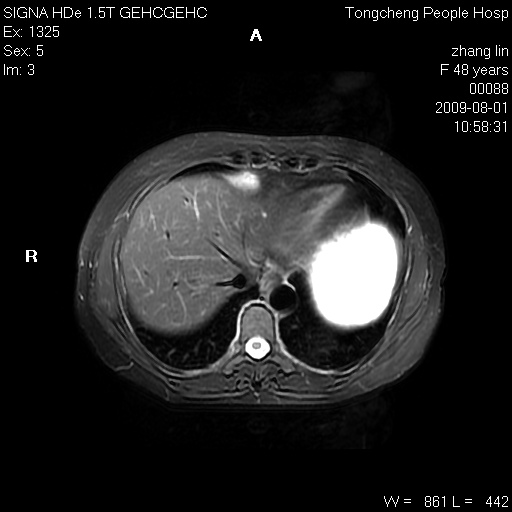

女,48岁。健康体检,彩超发现右肾占位性病变。平素健康。

临床诊断:右肾占位性病变,性质待定(囊肿?肿瘤?)。

上中腹部mr平扫+增强扫描,图像如下:

右肾上极见一类圆形病灶,t1wi呈等信号t2wi呈等高混杂信号,三期增强无强化,边界清---考虑囊肿出血。

同反相位均表现为等信号,病变无强化,考虑含蛋白的囊肿可能,弥散加权相或许有些帮助,

慢性胆囊炎